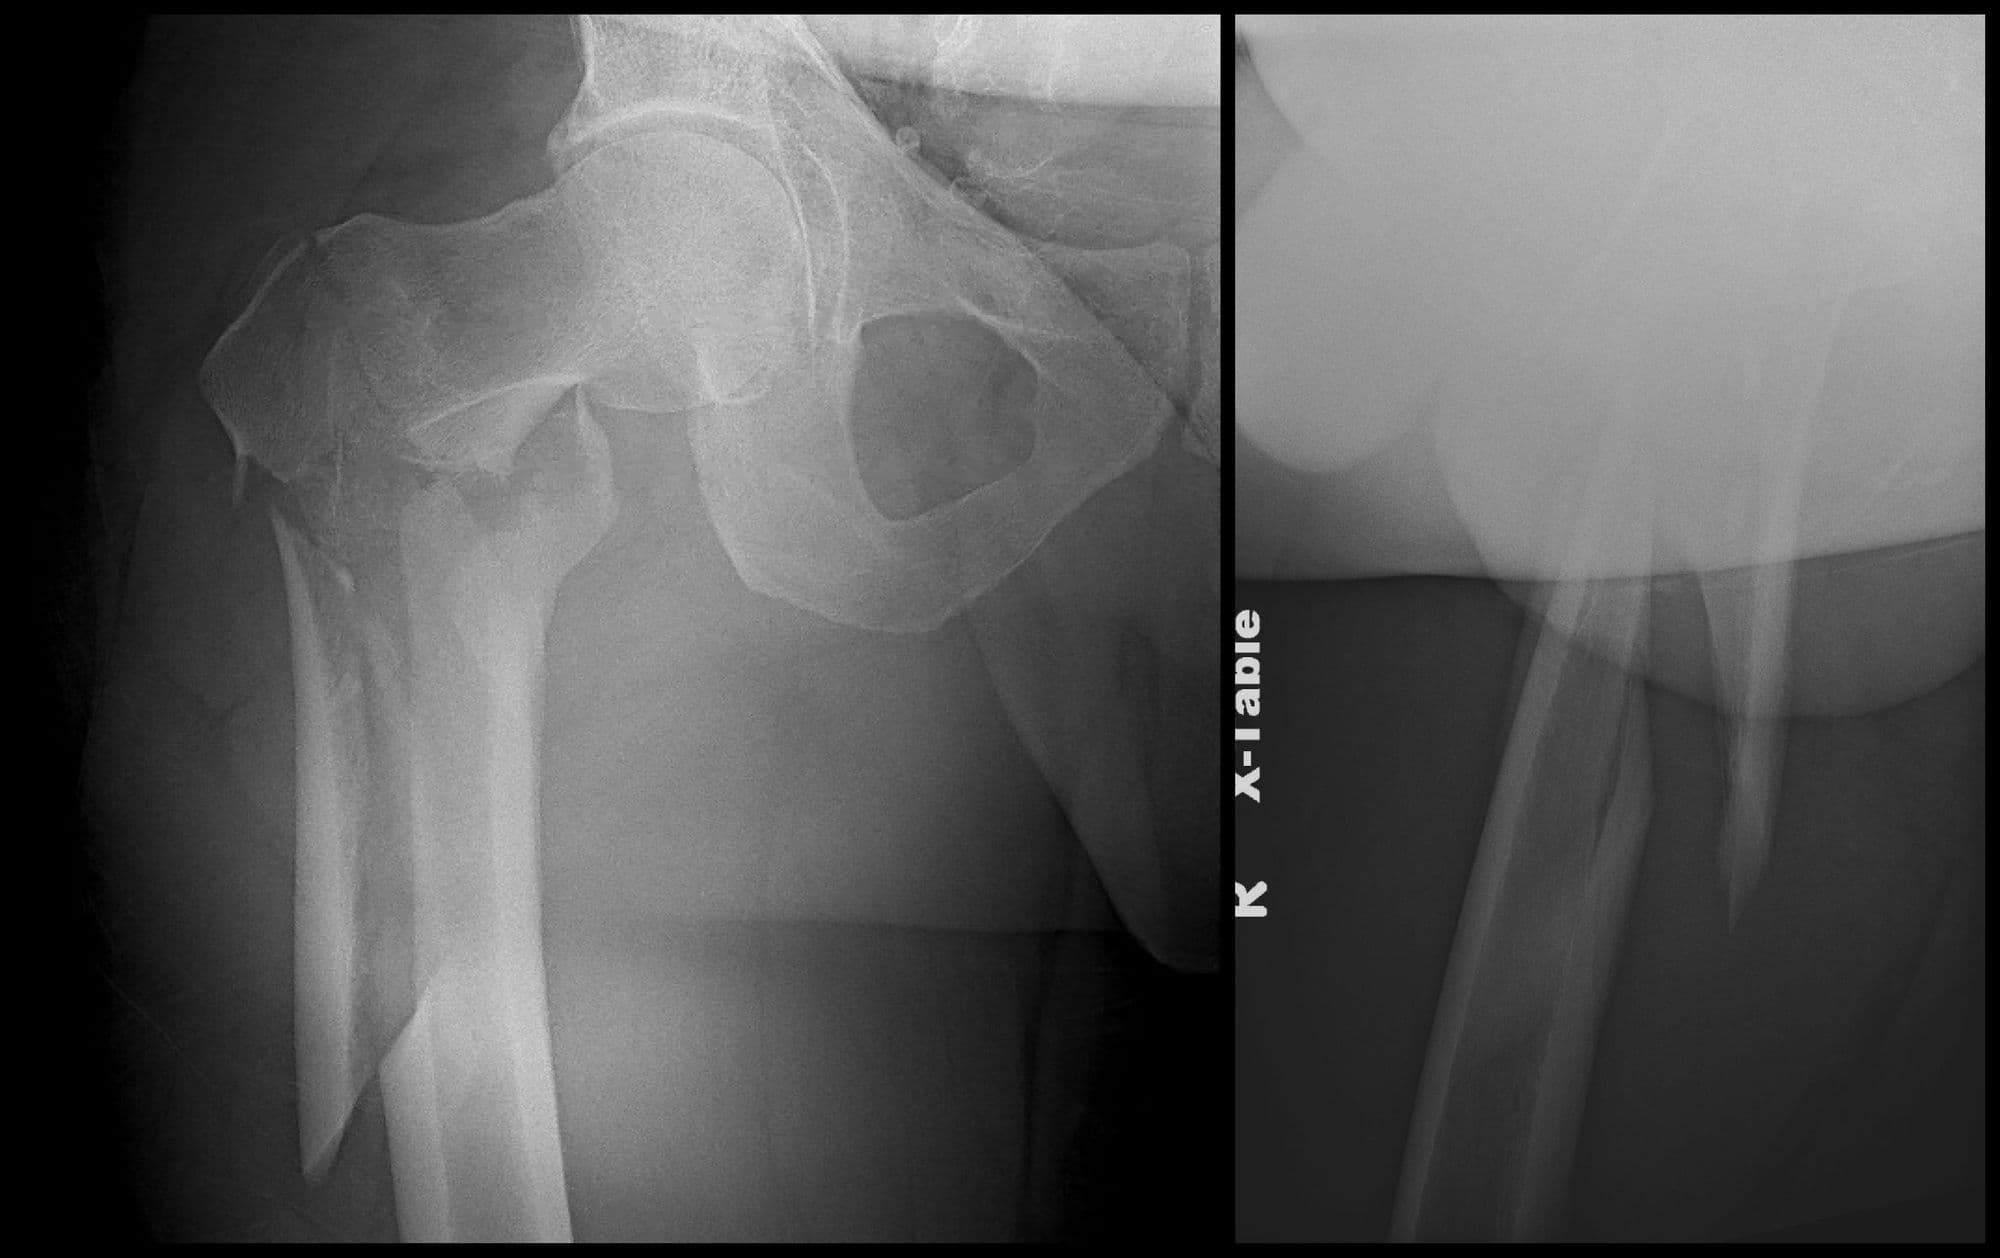

Intertrochanteric Fracture Short Nail

Pre-op